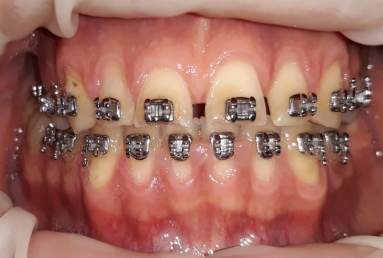

Then fixed orthodontic treatment is set for almost 2 years, so moving the teeth a new more favorable position is obtained to create space for veneers. After wax up a mock up is done for provisional veneers and the new occlusion is tested.